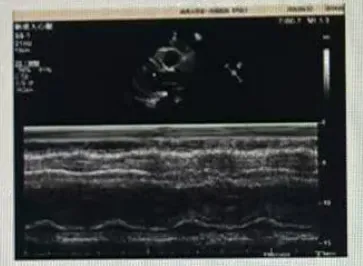

超声所见:各房室腔内径正常范围,室间隔及左室壁增厚,运动协调,收缩幅度正常。各膜形态、结构、运动未见异常。升主动脉增宽,余大动脉关系、内径正常。心包腔未见异常。

检查提示:升主动脉增宽;室间隔及左室壁增厚;主动脉瓣大量反流、二尖瓣反流(均少量);主动脉瓣狭窄(重度)。